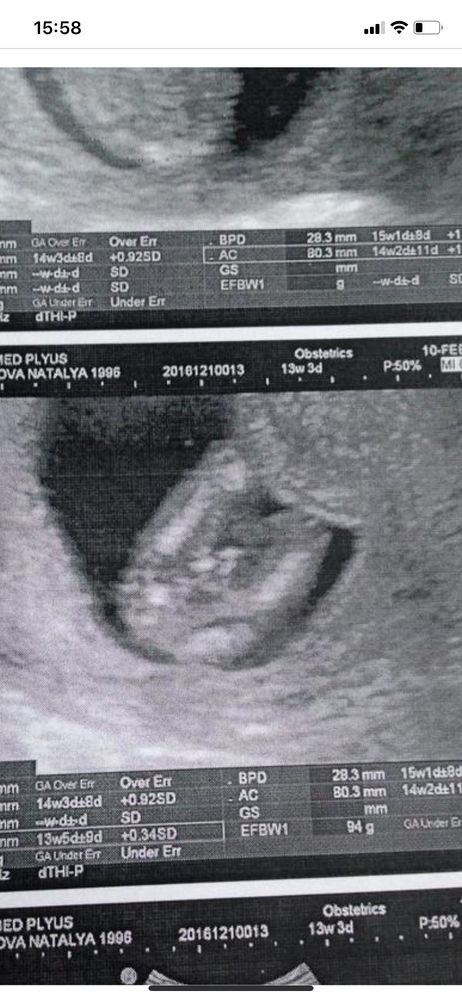

Вторя беременность

Сегодня была на скрининге 13 нед по мес, и 12 по фотометрию.

Все отлично, но пол сказали мальчик.

Я вот думаю, может ещё пол не точный? Может поменяется все там? И сравниваю фото узи

На таком сроке у всех хвостики между ног, нужно смотреть градус под которым лобок, по вашим картинкам этого не распознать 🤷🏻♀️

Хоть ещё и небольшой срок,но все же я склоняюсь что у вас второй тоже мальчик))

Вот фото с узи в 13 недель,родился мальчик)